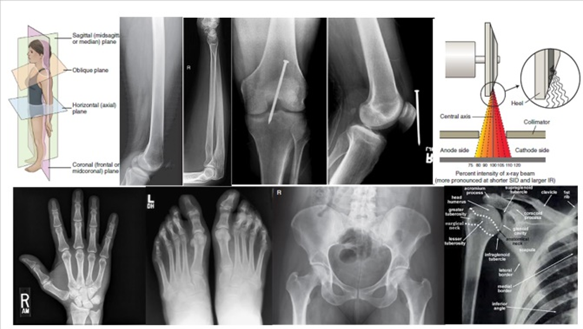

1. Introduction to Human anatomy

2. Skeletal system

This Medical Imaging Science Discipline Course is a continuation of the MRI Series in which the students develop their radiographic techniques in radiation imaging examinations. The students are introduced to chest, abdomen, head and spine radiography. Radiation Safety Practice and Image Quality Factors are further learnt in enhancing the student's competencies towards conventional radiography.

Medical Radiation Imaging II is a second year course under the Bachelor of Medical Imaging Science program and it introduces the undergraduates to imaging sciences in radiography, specifically the imaging principles, techniques and skills, and radiation protection involved in radiographic procedures and examinations of the axial region of the human anatomy. It is a continuation from MRI I and it covers Chest, Abdomen, Spine and Skull Radiography. Furthermore, it will also help the undergraduate to develop and enhance their written and oral communication (English). The course is significant as it establishes vital connections that enable students to complete the year of study through team effort and correlating with other courses for clinical applications.